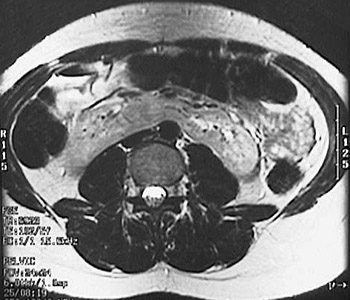

These abdominal MRI scans with contrast reveal a horseshoe kidney bridging across the midline. This was an incidental finding in an adult.